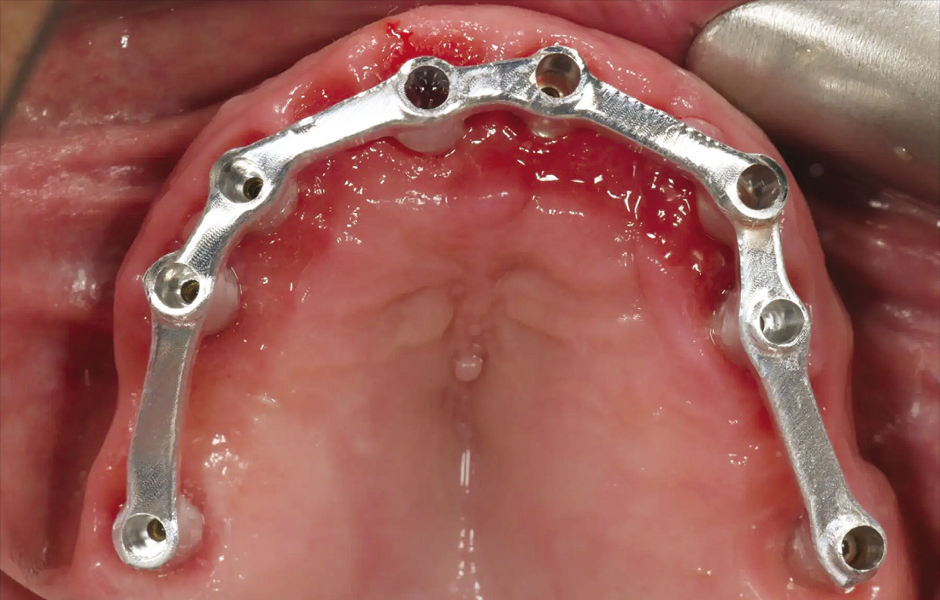

Obr. 6: Chirurgická šablona bez kovových pouzder pro přípravu fixačních pinů.

Obr. 7: Chirurgická šablona bez kovových pouzder pro plně navigovanou implantaci.

V den operace byla aplikována lokální anestezie a první chirurgická šablona byla stabilizována na zbývajících zubech k přípravě pěti fixačních pinů. Poškozené zuby byly extrahovány a druhá chirurgická šablona byla upevněna v připravených místech. Osm implantátů (Osstem TSIII SOI, Osstem Implant) bylo umístěno – pět do čerstvých extrakčních alveolů a tři do dříve zahojených oblastí. Všechny implantace proběhly plně navigovaně pomocí chirurgické šablony bez kovových pouzder a s dedikovanou chirurgickou sadou (OneGuide KIT, Osstem Implant; obr. 8). [11] Jeden implantát vyžadoval krestální sinus lift, který byl proveden plně navigovaným přístupem (OneCAS KIT, Osstem Implant; obr. 9). Xenogenní kostní materiál (A-Oss, Osstem Implant) byl použit k vyplnění extrakčních alveolů a dutiny sinu. [12] Na všechny implantáty byly okamžitě nasazeny multi-unit abutmenty a dočasné abutmenty (Osstem Implant) podle konceptu „one abutment, one time“. [13] Předem připravená dočasná protetika na bázi PMMA s kovovou výztuhou byla vložena a ihned fixována v ústech. V ordinaci byly provedeny úpravy pro dosažení správné okluze (obr. 10–12). Pacient obdržel pooperační instrukce a medikaci.